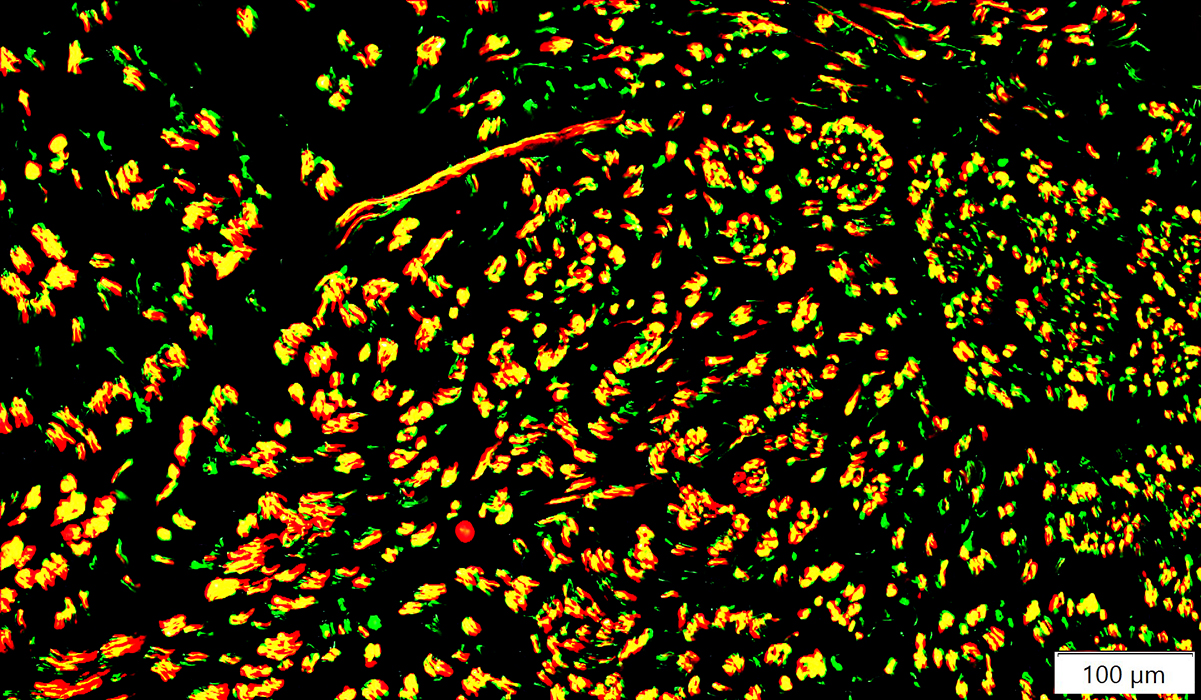

Neurofilament (Green); MBP (Red)

|

Immature Schwann Cells/Myelin: Express MBP in cells on axons with thin, or no, myelin

Small & Intermediate-sized axons

Many have associated MBP+ Schwann cells (Yellow)